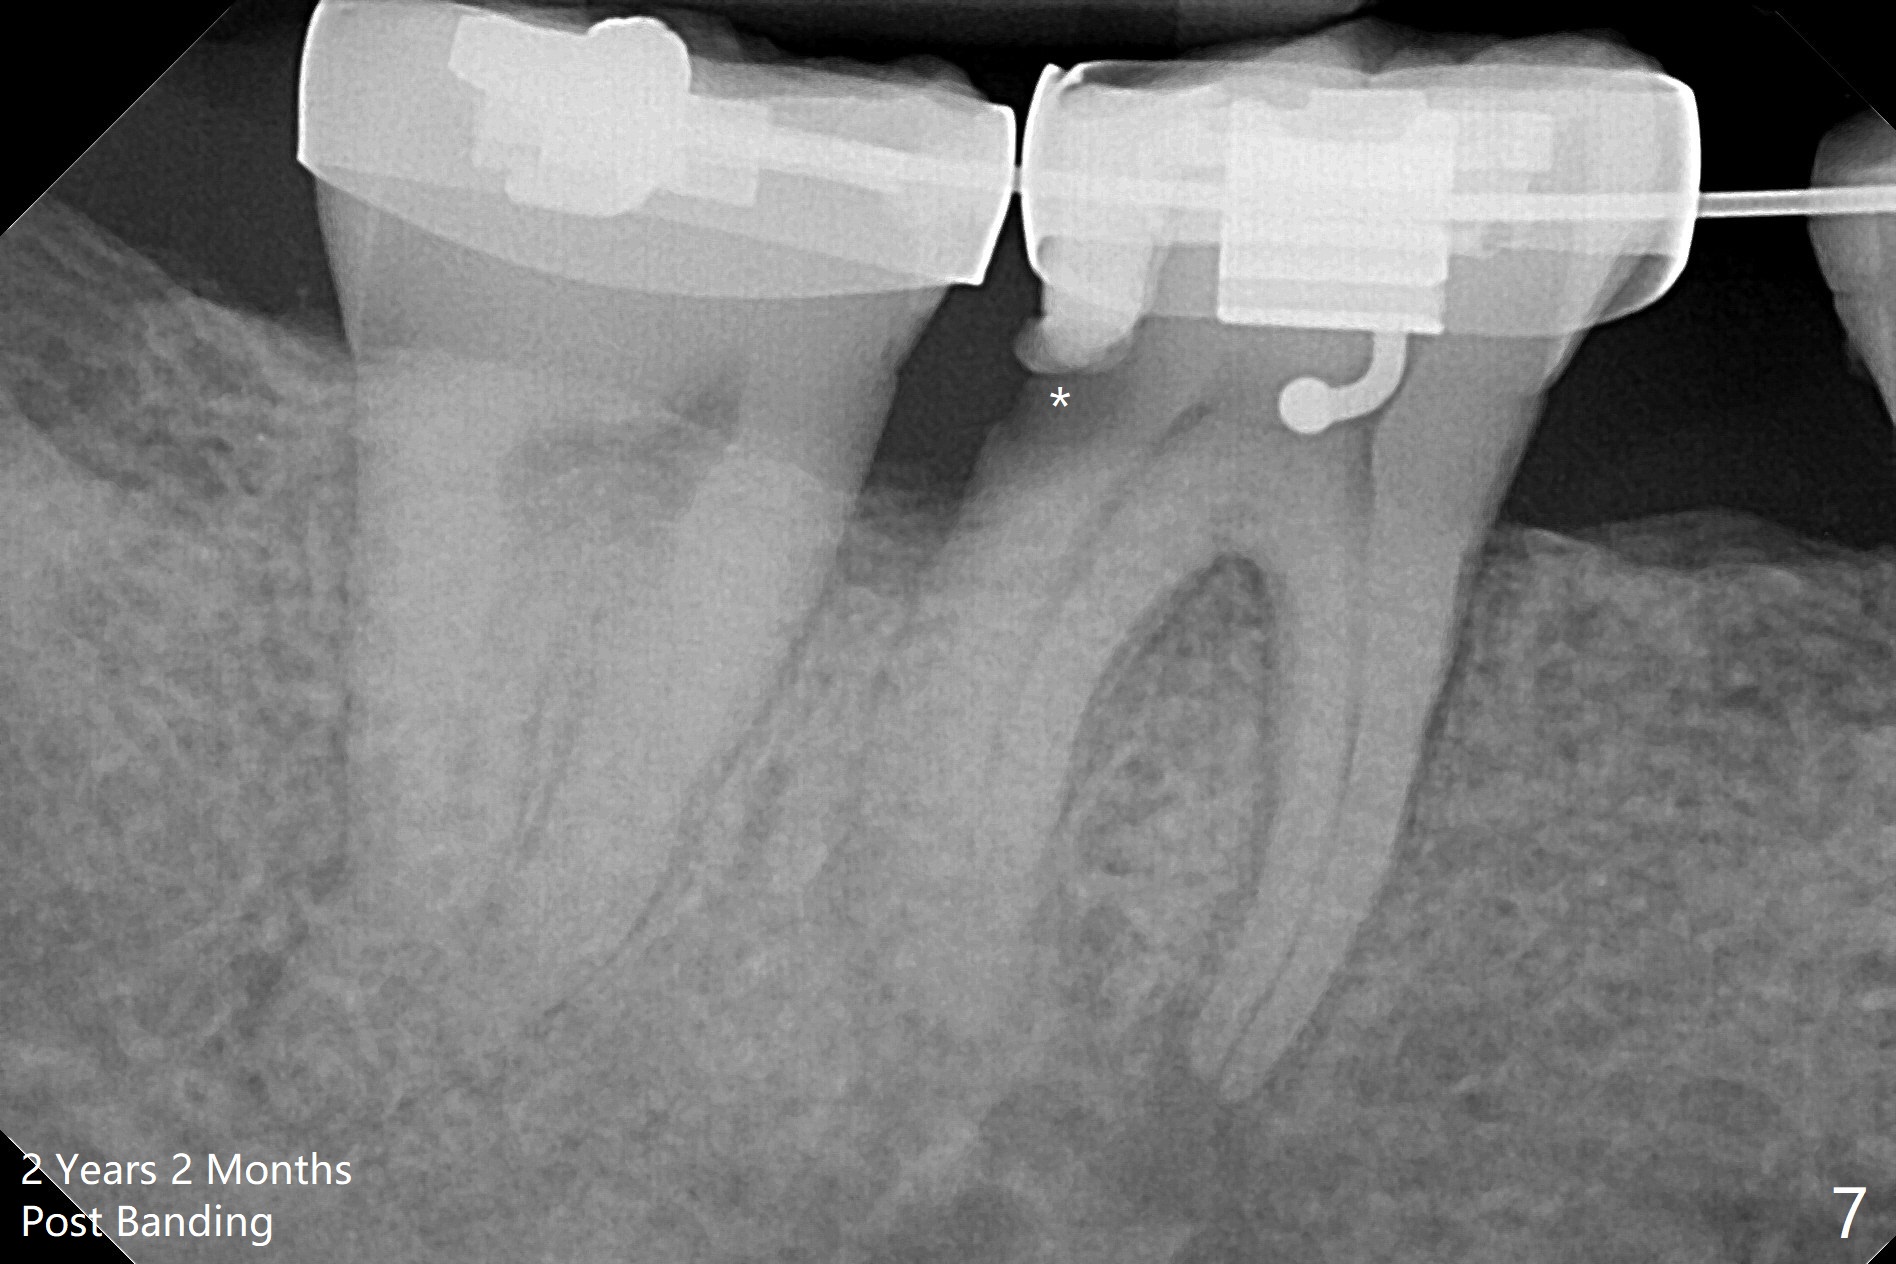

One year 4 months post banding (M) with 16x16 wires, UR3 is being distalized using UR7 as anchor (Fig.1), while the upper dental midline matches the facial one (Fig.2). The anterior overjet remains large (Fig.3). When UR3 is fully distalized, place posted wire to distalize U2-2 together. U2-2 distalization seems to be slow with one 16 mm closed coil spring each side (between 7 and post) 1 year 10 months post banding. Since the upper anterior PA shows mild root resorption at UR2 (Fig.4), a 14 mm closed coil spring is added each side (between 6 and post, Fig.5,6). LR6 has pain 2 years 2 months post banding (Fig.7). Debridement confirms non-salvageability; a 5x11.5 mm implant will be near the mesial root (Fig.8). Power chains for a month leads to closure of the gap between 3 and 4 (Fig.8-11). The space between 4 and 7 is 15 mm. A 12 mm 1st molar crown will be made, while the remaining 3 mm space will be closed by mesialization of 7 using 2 power posts mesial and distal to 6 and 7. Draw 2 tubes of blood. Make an incision to expose the mesial crest of 6.